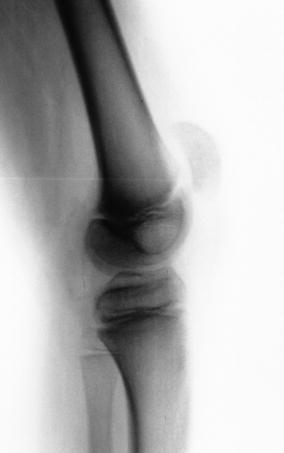

Four patients, all men, with a diagnosis of FKFD secondary to an underlying neurological or congenital disorder participated in this prospective IRB-approved study. Subject demographics are given in Table 1, and a preoperative radiograph of subject 1 is provided in Fig. 1. A standard marker model was applied, and data were collected using a ten camera motion capture system (Vicon, Centennial CO, USA) and four force platforms (AMTI, Watertown, MA, USA) as the subjects ambulated at a self-selected velocity along a 10-m walkway [16]. A standard physical examination by an experienced therapist was performed to measure passive range of motion at the knee, hip and ankle. The Gross Motor Function Measure (GMFM) Questionnaire sections D and E (standing/balance and walking) [17, 18] and the Gillette Functional Assessment Questionnaire (FAQ) [19] were administered to families, and the patients’ Gross Motor Function Classification System [20] was rated by a physical therapist. Within 1 month following the preoperative gait study, each subject subsequently underwent anterior distal femoral guided growth, placing a plate on either side of the patello-femoral sulcus.

Fig. 1.

Bilateral fixed knee flexion deformity of 18° causing obligatory crouch gait and associated anterior knee pain (subject 1)